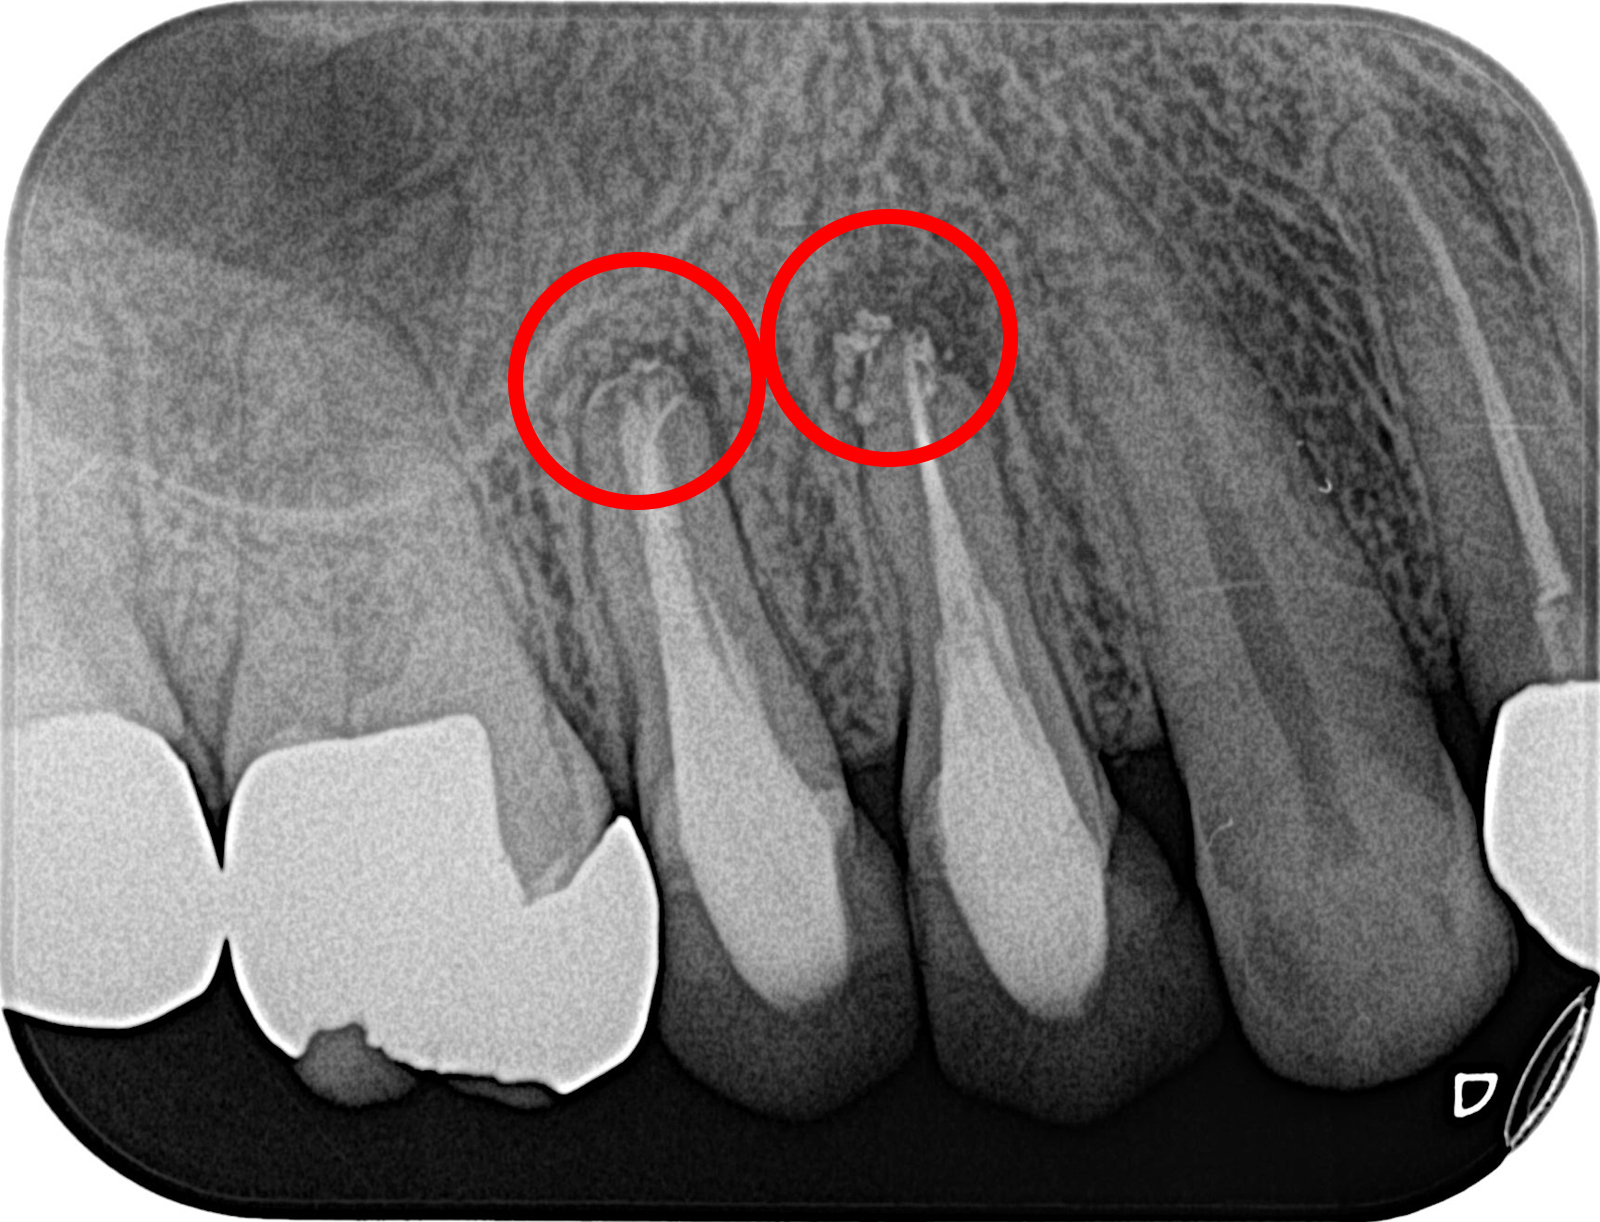

• 治療前

• 治療後

他院で根管治療を行ったが治癒せず、当院で歯根端切除を行いMTAセメントを充塡した。

術後8年後の様子。骨はきれいに再生している。